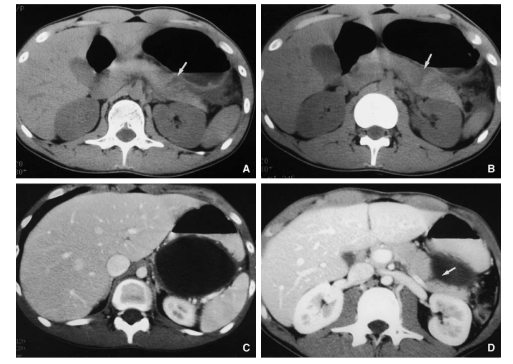

- CT và cho BN uống thuốc cản quang tan trong nước (Telebrix) 🡪 khối tụ dịch vùng quanh tá tràng và thận phải, thuốc cản quang lan ra ngoài

A – Thương tổn tụy độ II

B – Dẫn lưu HCMN, mở thông túi mật, mở thông dạ dày, mở thông hỗng tràng

A – Thương tổn độ I ở đầu tụy, độ III (AAST) ở D2

B – Khâu vết thương tá tràng D2, mở thông túi mật, mở thông dạ dày, mở thông hỗng tràng, dẫn lưu HCMN và cạnh tá tràng (theo C.Arvieux, C.Létoublon 2005)